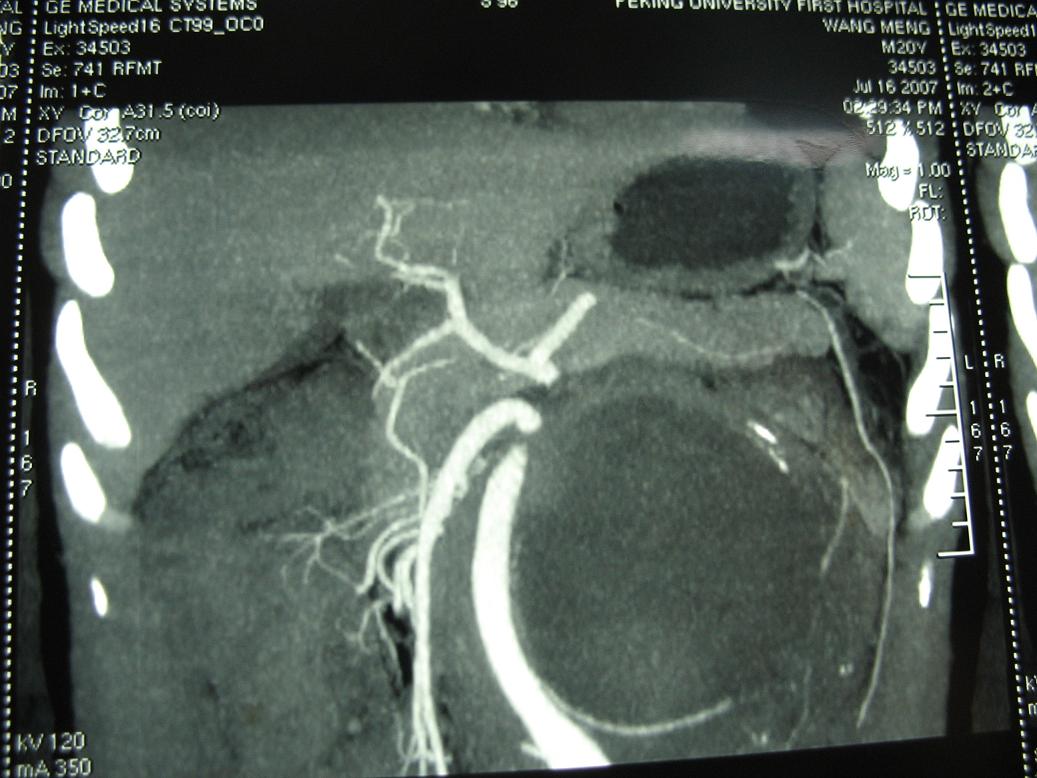

m20,发现腹部肿物二月.

2、左侧腹膜后囊实性占位性病变,有完整包膜,周围脏器及血管呈受压移位改变,左肾积水,肾实质变薄,增强扫描示病变包膜有强化,因图片太少,实性部分是否强化不好判断。

3、诊断:结合病人年龄,左肾改变考肿虑为输尿管受压肾积水时间长,左肾实质萎缩,病变未见明显外侵征象,本人首先考虑为神经源性瘤囊变可能性大。

定位肿瘤在腹膜后没问题,包膜完整与左肾门及腹主动脉关系密切。腹膜后未见明确异常增大淋巴结,左肾积水增大,但要考虑肠间质瘤就不是腹膜后的了,手术至少要普外和泌尿外科协作,术前必须把肿瘤血供再搞清楚一点才行,肿瘤性质和组织学来源是病理的事,之后影像再回头学习。

结果收到,肿块较大,密度不均,实性部分有强化,包绕腹主动脉推挤左肾,左肾集合系统受压改变,病灶长轴与腹主动脉平行,支持副神经节瘤,但不典型。